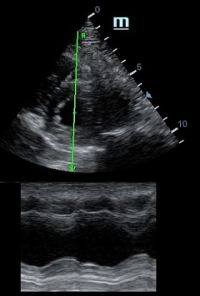

Но как же провести стандартные измерения в М-режиме, если мы его не использовали? На помощь приходит функция Free Xros M – анатомический М-режим. Имея записанную в память прибора видео петлю, мы можем провести линию М-режима в любом месте, при этом корректируя изначально не оптимальный угол.

Возможности применения функции многогранны: от измерения толщины стенок левого желудочка, движения створок митрального клапана и кооптации нижней полой вены до оценки сократимости миокарда как глобально, так и по сегментам.